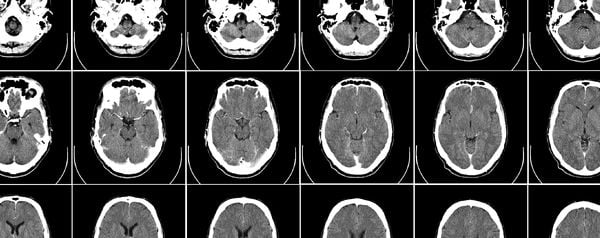

21 gezonde mannelijke en vrouwelijke proefpersonen met verschillende etnische en culturele achtergronden werden voor de studie onderzocht in een MRI-scanner terwijl ze naar afbeeldingen keken of naar muziek luisterden. Eerder hadden ze van dezelfde platen al aangegeven of ze deze ‘mooi’, ‘neutraal’ of ‘lelijk’ vonden. Die oordelen werden vergeleken met de resultaten uit de hersenscan.

Telkens bleek dat de mediale orbitofrontale cortex op de scans oplichtte bij kunst die eerder als ‘mooi’ werd aangemerkt. Opmerkelijk is dat muzikale en visuele kunst het deel voorin de hersenen in gelijke mate lijken te beroeren. “Vrijwel alles kan als kunst worden beschouwd, maar we denken dat alleen creaties die activiteit in de mediale orbitofrontale cortex teweeg brengen als ‘mooi’ kunnen worden geclassificeerd,” zegt Zeki. Daarmee is er natuurlijk geen objectieve definitie voor pracht gesteld, maar het lijkt nu toch bewezen dat discussie over persoonlijke voorkeuren vrij nutteloos is.

Overigens zijn er bij het waarnemen van schoonheid nog andere hersengebieden actief. Op MRI-scans licht bij het aanschouwen van kunst ook het hersengebied op dat vooral met romantiek wordt geassocieerd: de nucleus caudatus. Een relatie tussen de beleving van liefde en de beleving van schoonheid ligt voor de hand, maar moet nog verder worden onderzocht.